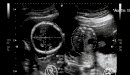

في هذه الفترة من عمر الجنين يُصبح شكله أقرب ما يكون إلى الطفل الرضيع مع اختلاف الحجم، حيث يكون وزنه ما يقارب 453.59 غم، ويبلغ طوله حوالي 27.94 سم، ويُمكن رؤية ذلك عن طريق التصوير بالموجات فوق الصوتيّة، أمّا العيون فقد تكوَّنت أجزاؤها البصريّة جميعها ما عدا القزحيّة، حيث لا تحتوي بعد على أيّة صبغة، وتكون الجفون والحواجب قد تكوَّنت.[٢]

مع بداية الأسبوع الثالث والعشرين يبدأ وزن الجنين وطوله بالزيادة ليقارب حجمه حجم فاكهة المانجو الكبيرة، أو الجريب فروت، ويبدأ الجنين بالتحرُّك والرقص خصوصاً عند استلقاء الأم على ظهرها، وعلى الرغم من تطوُّر الرئتَين إلّا أنَّ الجنين لا يستيطع الاعتماد عليهما لإتمام عمليّة التنفُّس، ولكنَّه يُؤدِّي بعض حركات التنفُّس في هذه المرحلة، ومن ناحية أخرى يبدأ الشعر الناعم الذي يُغطِّي جسم الجنين باتِّخاذ لون أغمق، ومن الممكن رؤيته، وتمييزه بصورة الموجات فوق الصوتيّة.[٣]